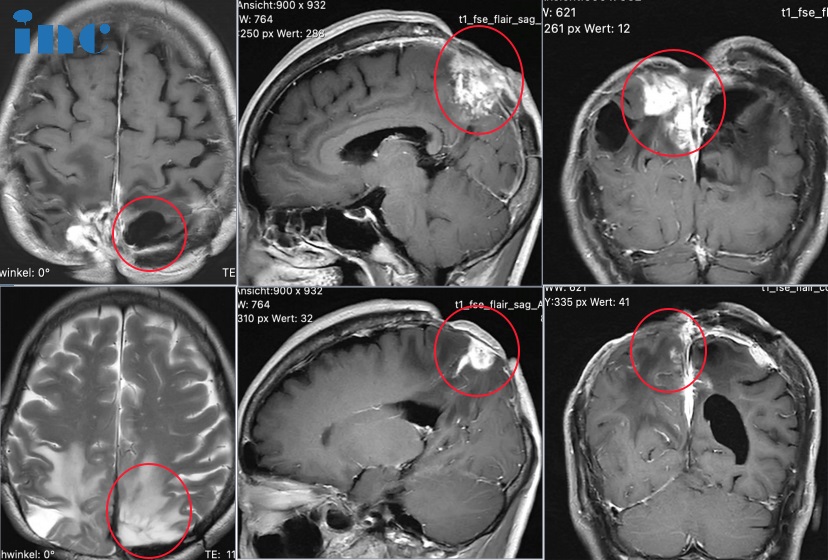

54岁女性-大脑镰旁脑膜瘤,2次开颅、放疗再次复发还有解决办法吗?

唐女士今年54岁,罹患顶叶脑膜瘤17年。较开始在北京某医院进行开颅手术,术后行放疗十余次后因伤口愈合不良终止。因皮肤溃烂诱发颅内感染,再次新开颅去骨瓣减压术及皮瓣移植术。后来病情出现反复,2020年 8 月出现走路不稳,细致动作差,行头颅 MRI 提示右枕部颅脑术后改变,左侧顶部大脑镰异常信号,怀疑脑膜瘤,再次行开颅手术。术后病理肿瘤浸润脑组织,WHO I-II 级(ki67 小于5%)。两次开颅均出现术后伤口愈合不良,癫痫也反复发作。

2021 年肿瘤再次复发,遂于北京某医院行伽玛刀治疗,放疗 2周后出现皮肤伤口溃烂。2023 年6月15日复查增强 MRI,双侧镰旁可见明显强化,较大截面积 3.0*2.9cm,较 2021 年12月有所增大。17年间2次开颅手术,2次放疗,期间多次复发。肿瘤和之前的治疗对大脑造成的损伤也导致唐女士行走不太稳、辨距不良、平衡感差等等。病情之复杂,唐女士不知道自己的病还有没有其他办法可以治疗。

巴教授在远程咨询中也为唐女士做了详细评估。从临床角度来看,患者目前的情况不需要紧急治疗。然而,从长远来看,由于局部残留肿瘤--复发或残留的大脑镰脑膜瘤--以及多次手术后的脑水肿和皮肤问题,患者可能需要再次治疗。如果要对该肿瘤进行手术,他将尝试98-99%的切除率(包括受累的大脑镰)。

再次面对面咨询时,当得知唐女士目前正在服用一种抗血管药物,如果要做手术,是要把抗血管药物停掉了5到6周以上才能做手术,这样才能风险降到较低,不然开颅出血这个风险很高。建议再复查,如果体积变大了,再做手术也是没有问题的。